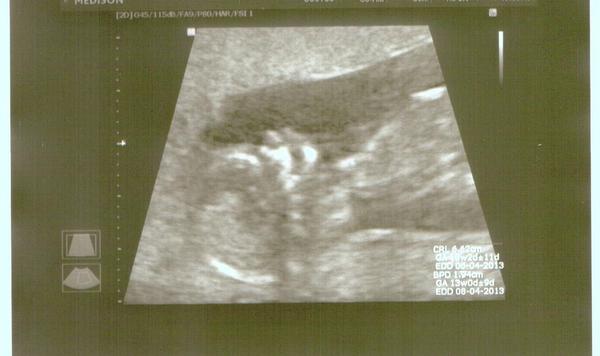

Hezké ráno všem. 🙂 @saraha2 Tak paráda manža bude mít partáka a ty si na čančací slečnu budeš muset počkat do píště 😉 (jako já) @pupidu Tak já měla nevolnosti skoro hned,někdo okolo 6tt jiný kolem 8tt,ale pokud nemáš vubec dojít nemusí-užívej si to 🙂 @pawlla Tak to jsme dvě já už ráno zas čučela nad WC,ale nějak jsem to zatím rozdejchala,ale cítím to pořád.(Na prázdnej žaludek to jde dost blbě) @mmiruda Kdepak máme ospalku Miruš 😀 Asi dělá dětem snídani. Jinak ve čtvrtek mně čeká krev na štitku,před poslední kontrolou v těhu-pak až po porodu,chodila jsem co 5-6týdnu.,v neděli Fecha srdíček a v pondělí kontrola u gyn a pak už budu chodit co 14dnu.Jen ten malíř mně se.. už naněj čekám jak na smilování,jinak nebudu schopna ani poklidit 😝 pupek roste.Jo a blíží se Brrr test na Cukračku 😝 že @danny38

@saraha2 tak to mas pekne aktivni miminko to muselo byt mooooc pekne, ja jsem videla zatim vzdy jen tecku nebo malou smouhu na utz tak se tesim az taky uvidim jak se to tam vrti 😀